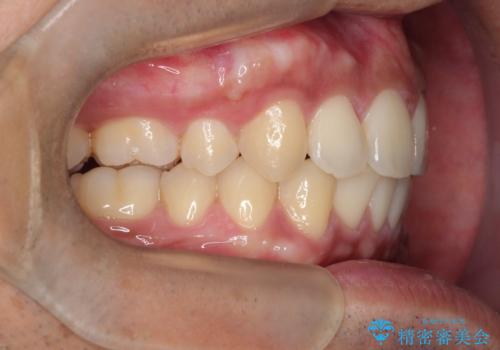

- 歯並びの凸凹を主訴に来院されました。

スペースが必要なため、抜歯を行なって治療を行いました。

奥歯の捻れが強く治療期間がかかりましたが、綺麗な仕上がりに満足していただきました。